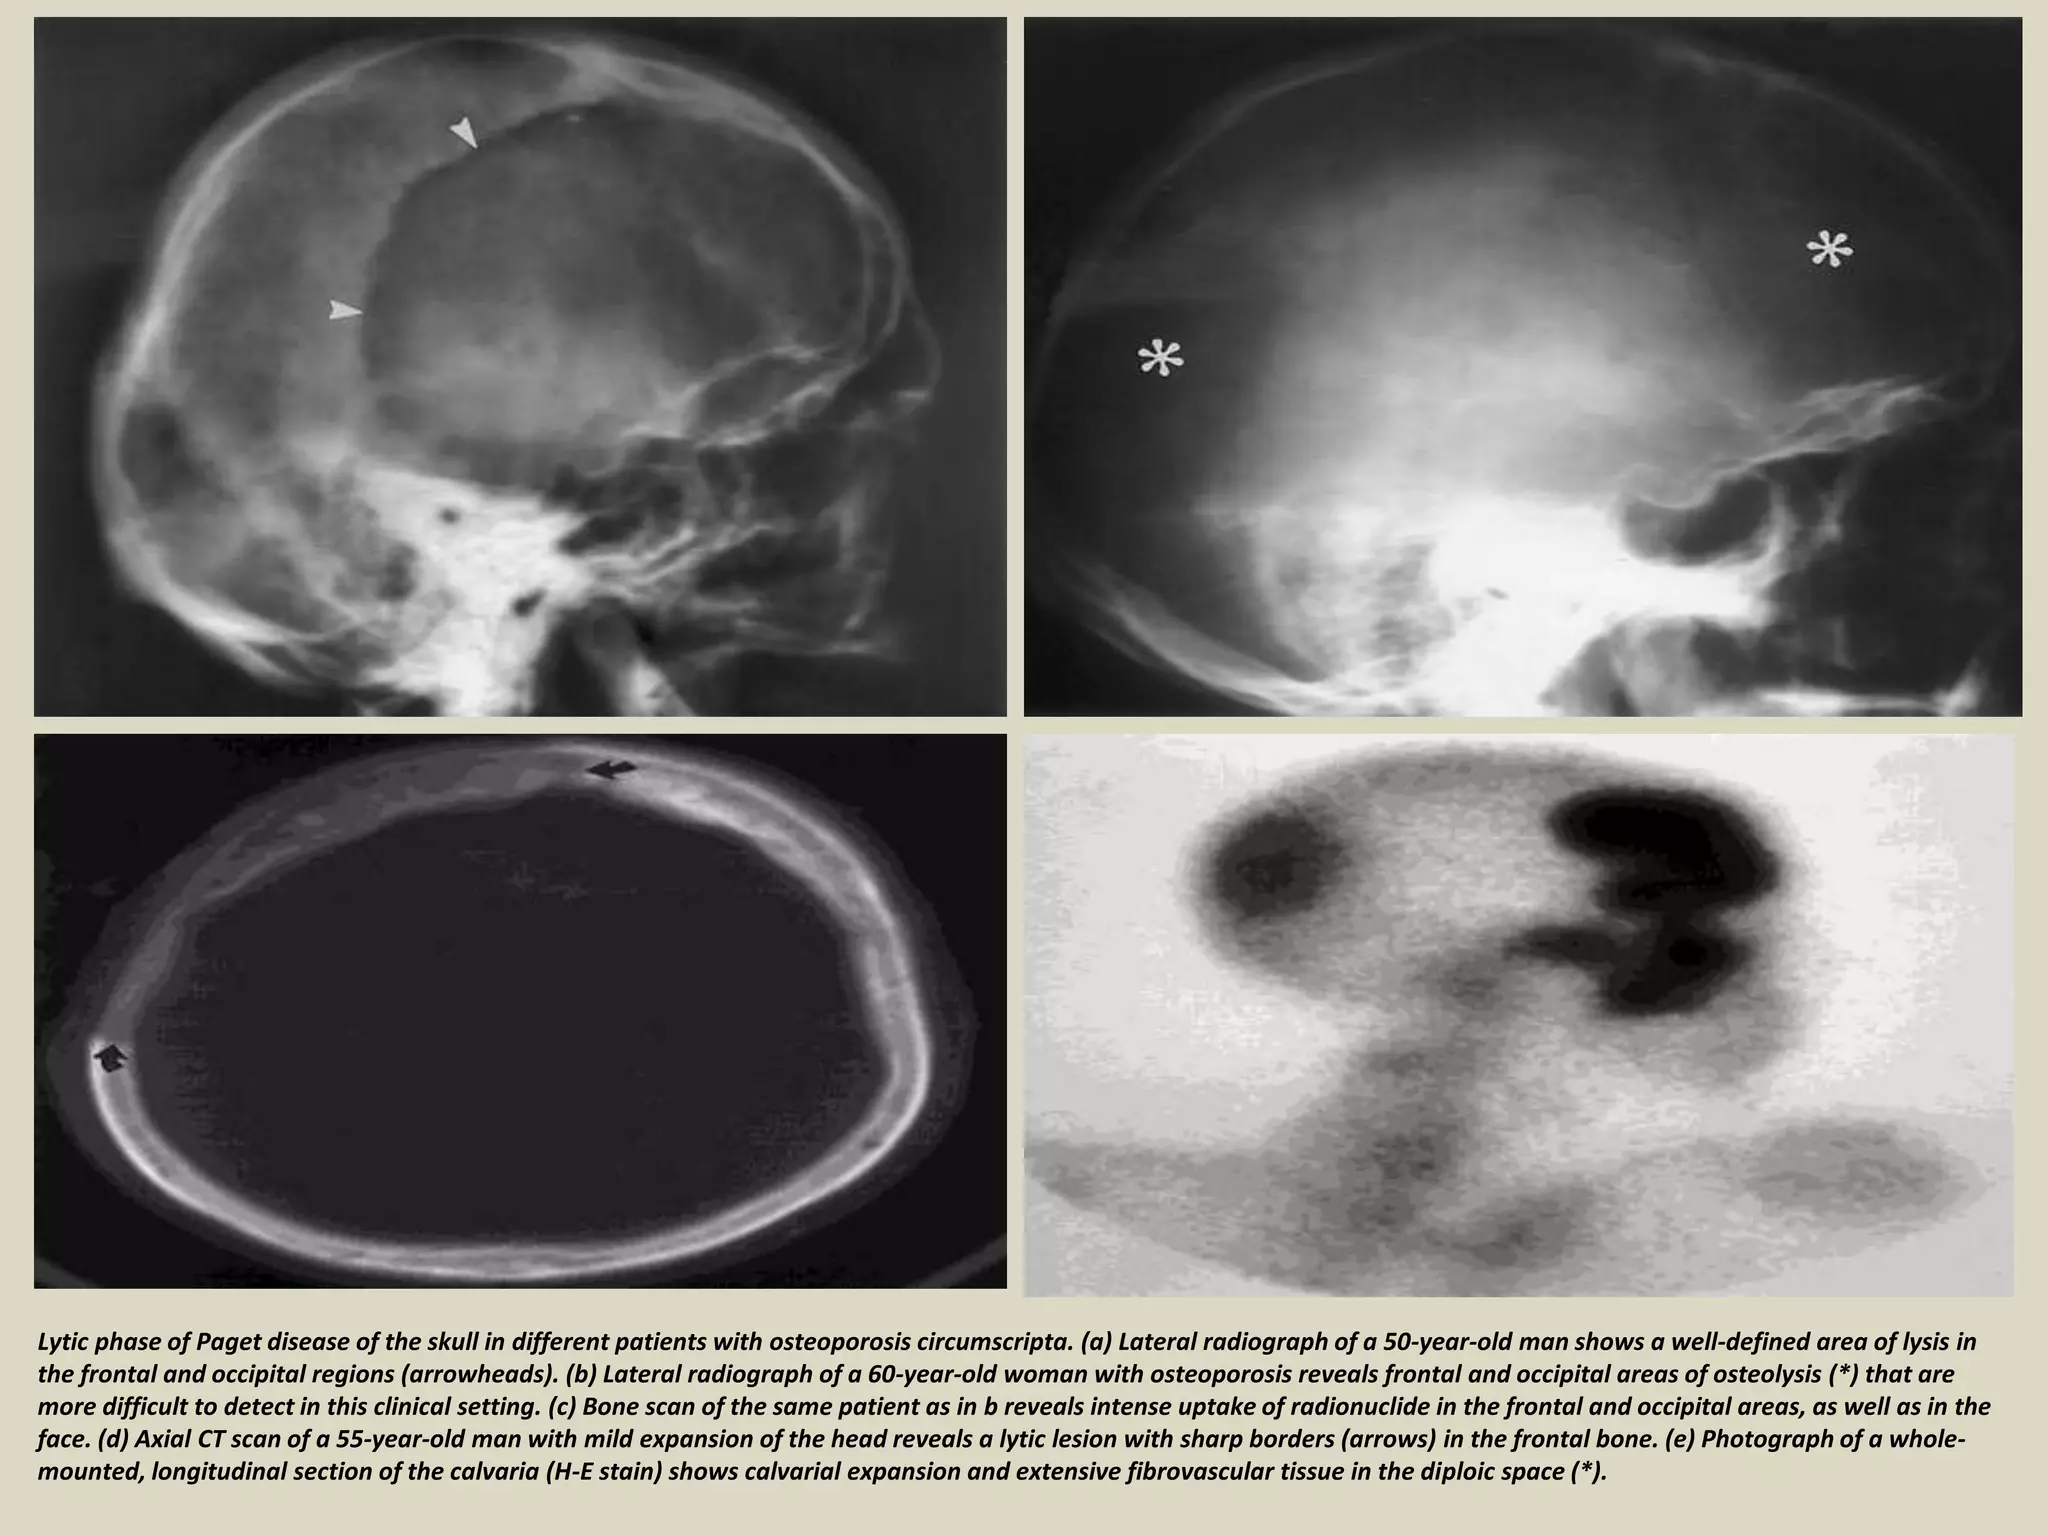

Lytic phase of Paget disease of the skull in different patients with osteoporosis circumscripta. (a) Lateral radiograph of a 50-year-old man shows a well-defined area of lysis in

the frontal and occipital regions (arrowheads). (b) Lateral radiograph of a 60-year-old woman with osteoporosis reveals frontal and occipital areas of osteolysis (*) that are

more difficult to detect in this clinical setting. (c) Bone scan of the same patient as in b reveals intense uptake of radionuclide in the frontal and occipital areas, as well as in the

face. (d) Axial CT scan of a 55-year-old man with mild expansion of the head reveals a lytic lesion with sharp borders (arrows) in the frontal bone. (e) Photograph of a whole-

mounted, longitudinal section of the calvaria (H-E stain) shows calvarial expansion and extensive fibrovascular tissue in the diploic space (*).